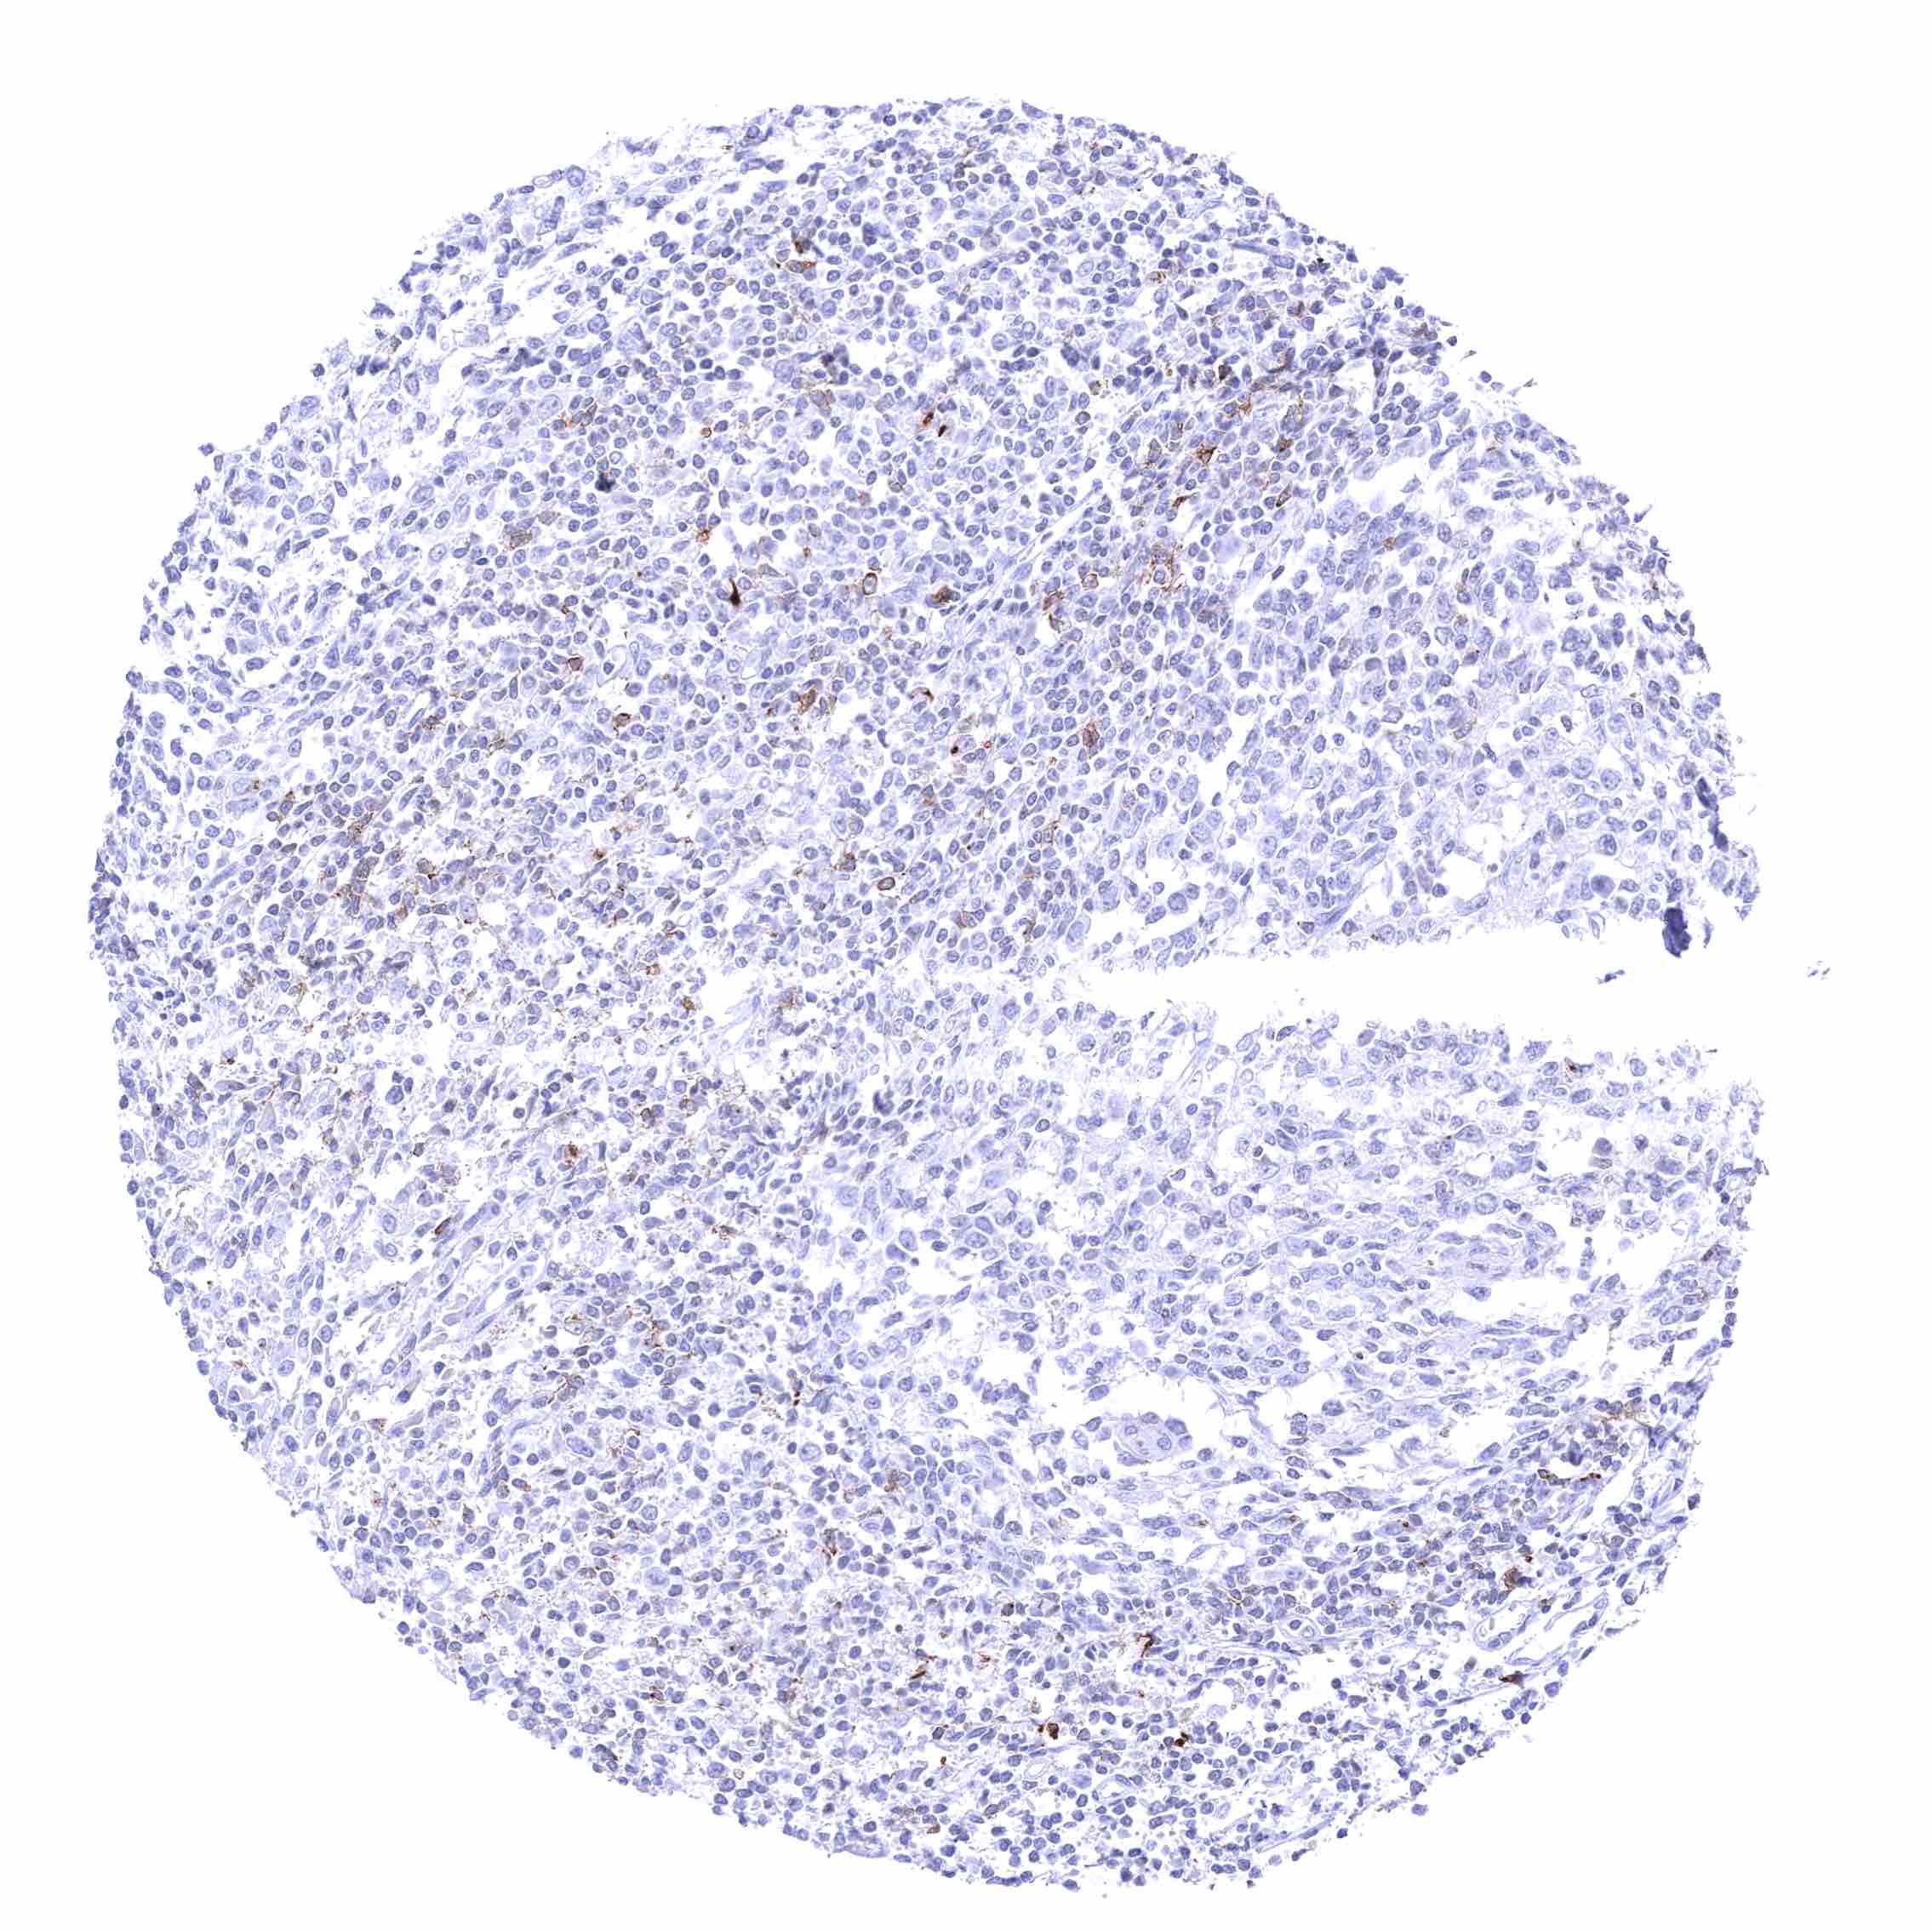

Lymph node – Membranous CD70 staining of variable intensity in subsets of cells (mostly lymphocytes). Most CD70 positive cells are interfollicular.